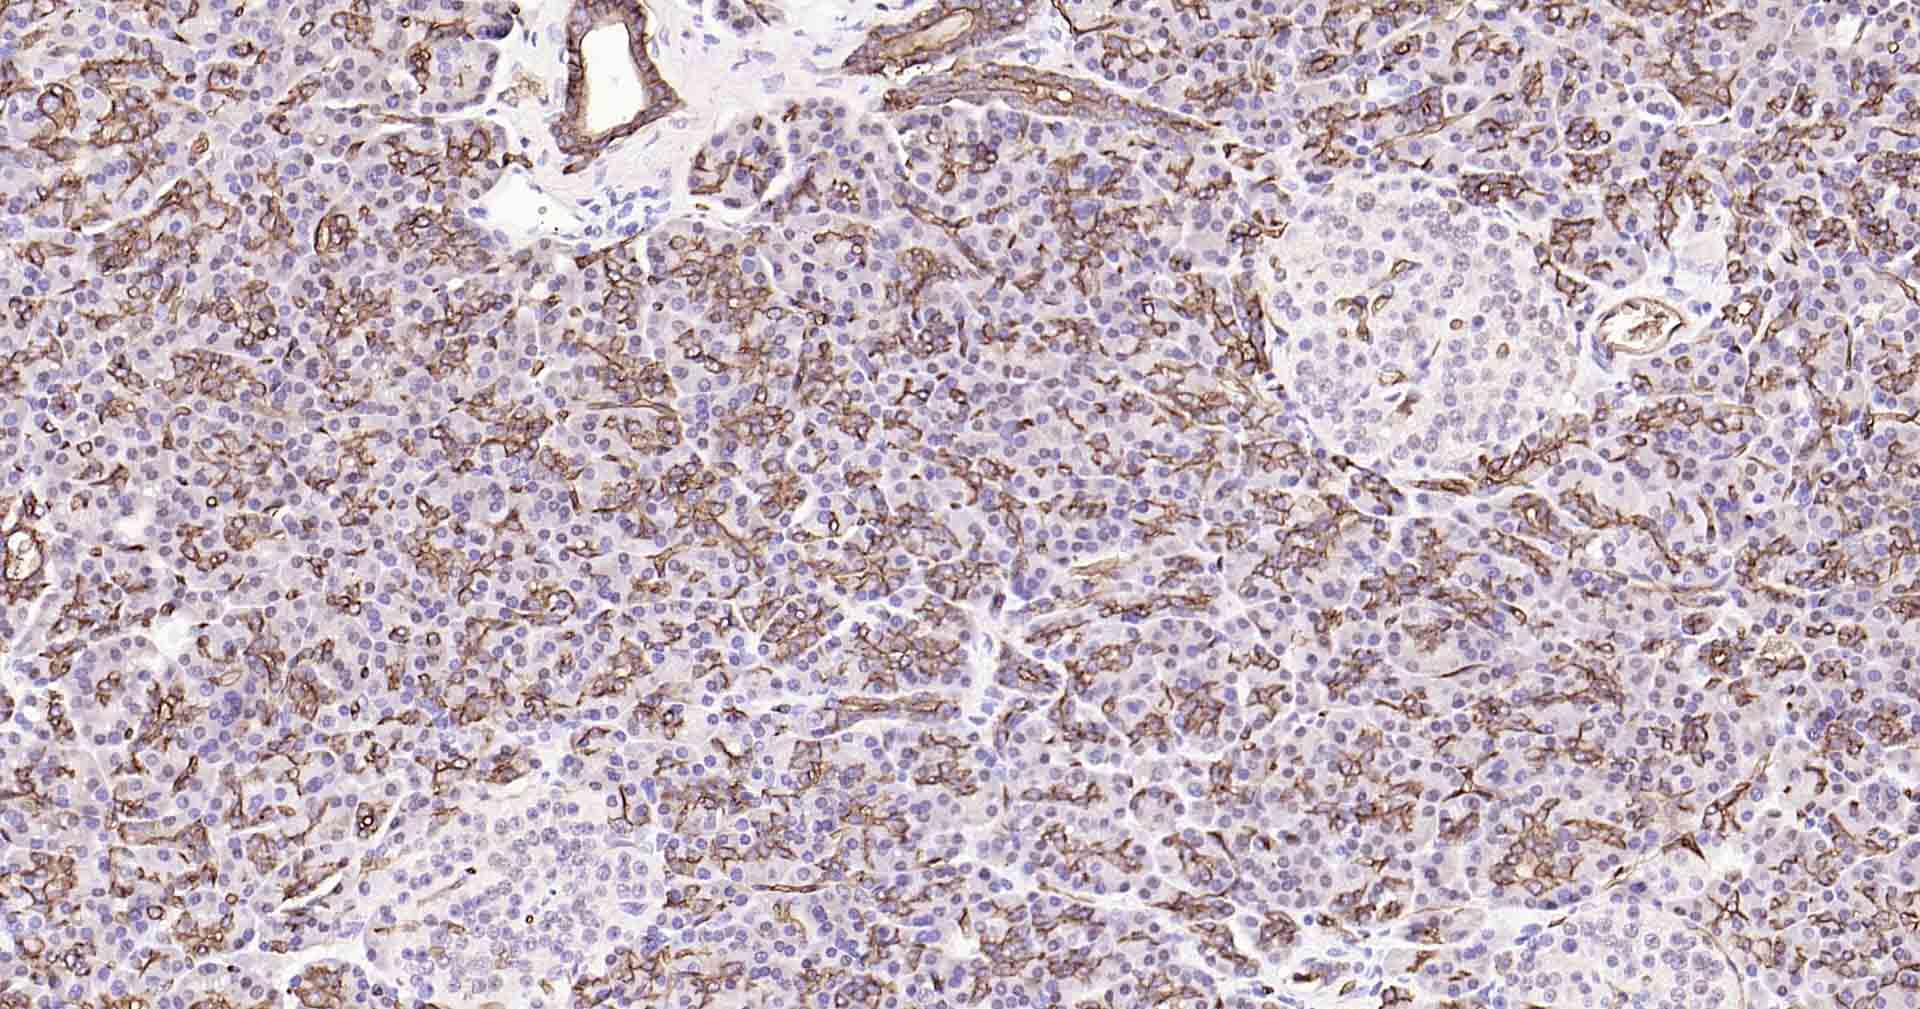

Paraformaldehyde-fixed, paraffin embedded Human Kidney; Antigen retrieval by boiling in sodium citrate buffer (pH6.0) for 15 min; Antibody incubation with AQP1 Monoclonal Antibody, Unconjugated(bsm-52909R) at 1:200 overnight at 4°C, followed by conjugation to the SP Kit(Rabbit, SP-0023) and DAB (C-0010) staining.

Paraformaldehyde-fixed, paraffin embedded Rat Kidney; Antigen retrieval by boiling in sodium citrate buffer (pH6.0) for 15 min; Antibody incubation with AQP1 Monoclonal Antibody, Unconjugated(bsm-52909R) at 1:200 overnight at 4°C, followed by conjugation to the SP Kit(Rabbit, SP-0023) and DAB (C-0010) staining.

Paraformaldehyde-fixed, paraffin embedded Mouse Kidney; Antigen retrieval by boiling in sodium citrate buffer (pH6.0) for 15 min; Antibody incubation with AQP1 Monoclonal Antibody, Unconjugated(bsm-52909R) at 1:200 overnight at 4°C, followed by conjugation to the SP Kit(Rabbit, SP-0023) and DAB (C-0010) staining.